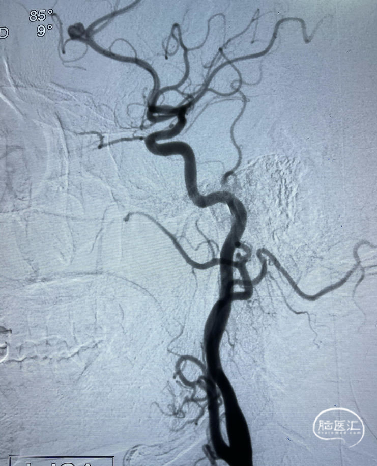

DSA:左侧大脑前动脉A2-A3动脉瘤(分叶状)

![]() 后循环造影